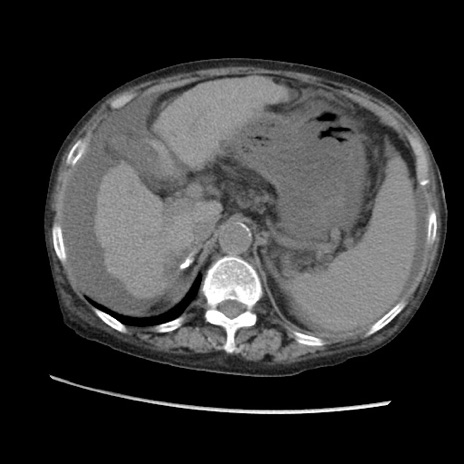

冠状断像

【症例】80歳代 女性

【主訴】腹部膨満感

【現病歴】他院にて肝硬変にてフォロー中。1週間前から便秘、腹部膨満感、臍部腫瘤あり受診となる。

【既往歴】肝硬変

【身体所見】腹部膨隆あり、皮膚変化なし、疼痛なし。

【データ】WBC 4600、CRP 0.25